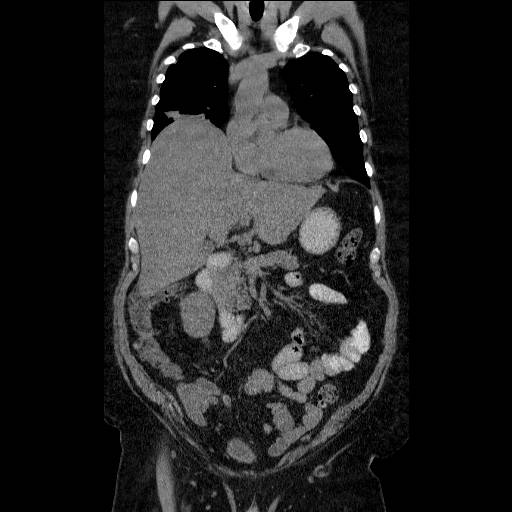

Lever, Metastaser, CT og Ultralyd

CT- og UL-skanning af leveren uden kontrast. CT (nedenfor) viser stor lever, men UL (ovenfor) viser variende ekkoer forenelig med metastaser. CT-diagnostik af levermetastaser kræver administration af kontraststof og skanning i den rette fase af kontraststoffets passage af leveren.